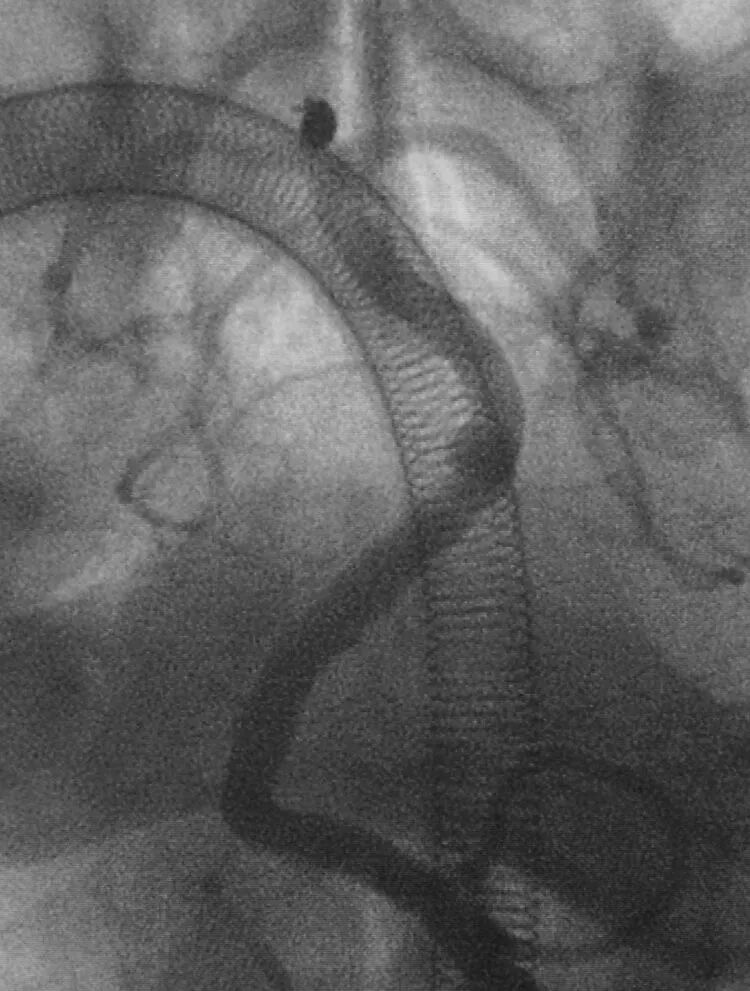

眼动脉瘤,位于颈内动脉虹吸弯前膝稍远心端,向上方生长